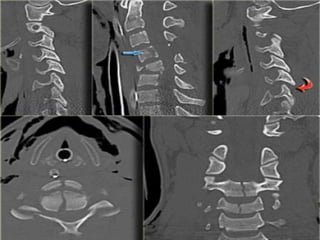

CT IMAGE

DENS

The image through the lateral part of C2 nicely shows, that the fracture runs

through the body of C2, i.e. a type III odontoid fracture.

The posterior dura is in a normal position, but the anterior dura is displaced

(arrow).